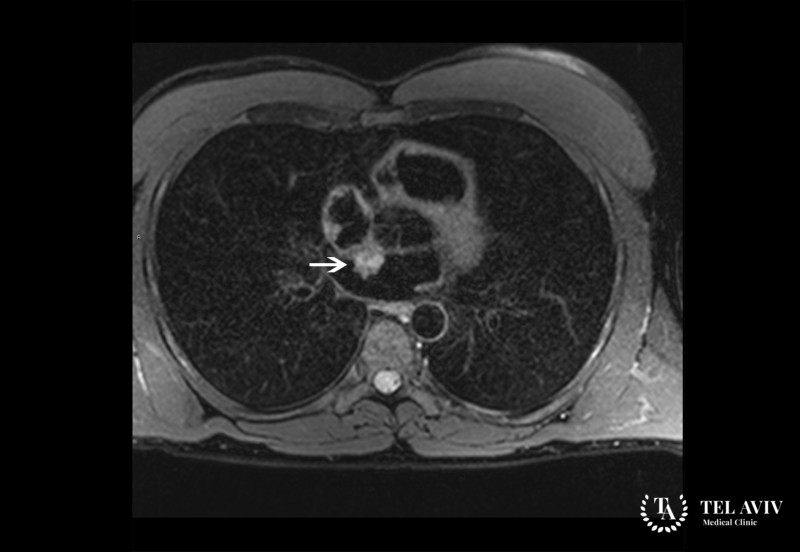

- МРТ.

Поскольку для опухолей сердца типичны одни и те же признаки, обследование должно проводиться особенно детально, чтобы среди множества морфологических форм выявить истинную патологию. Для тщательного диагностирования в израильской клинике Tel Aviv Medical Clinic имеется новейшая, специализированная аппаратура, позволяющая добиваться 100% достоверного результата. С помощью передового оборудования мы проводим визуализирующие исследования, используя лабораторную и инструментальную диагностику: